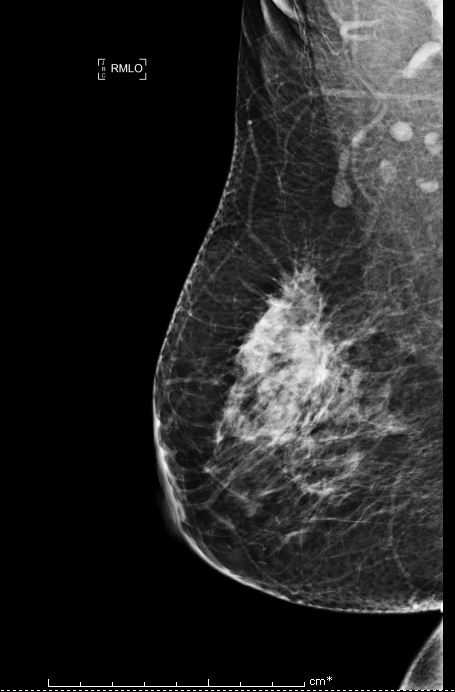

Bi-rads 4 means that the findings on the image are suspicious and that there is an approximately 20 percent to 35 percent chance that a breast cancer is present.

We proceed to calculate the volume of the tumor contained in the breast from the following Bi-rads 4 breast images.

We provide an algorithm that estimates the volume of the tumor contained in the breast. From the input of the digital tomosynthesis image, we expressed the ratio of tumor tissue to normal tissue as a function of the threshold in order to segment the region of interest, that is the region of the breast that contained the tumor (Figure: 3). We expressed the volume of the tumor as a function of the threshold. We, then, determine the optimal threshold upon which the volume of the tumor can be measured by looking at the rate of the tumor growth function.

The threshold upon which the tumor growth function changes direction for the first time yields the optimal threshold for the rapidly decreasing volume function. Since the X-ray light transmitting through the tumor region is proportional to the density of the tumor region by the Beer-Lambert Law, and that density of that tumor region is inversely proportional to the volume of the tumor region with the mass being constant by the equation- Density = Mass/Volume, then, the optimal threshold is at which yields the volume of the tumor to be about of the breast volume.